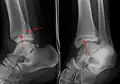

AP manual stress view showing a deltoid ligament tear

A specialized AP stress view of the ankle is performed when there is concern for an unstable ankle injury. There are two types of stress views: gravity and mechanical.[10] In the gravity stress view, the patient lies in the lateral decubitus position with the ankle dangling over the edge of the table to mimic the mechanical stress view.

Findings